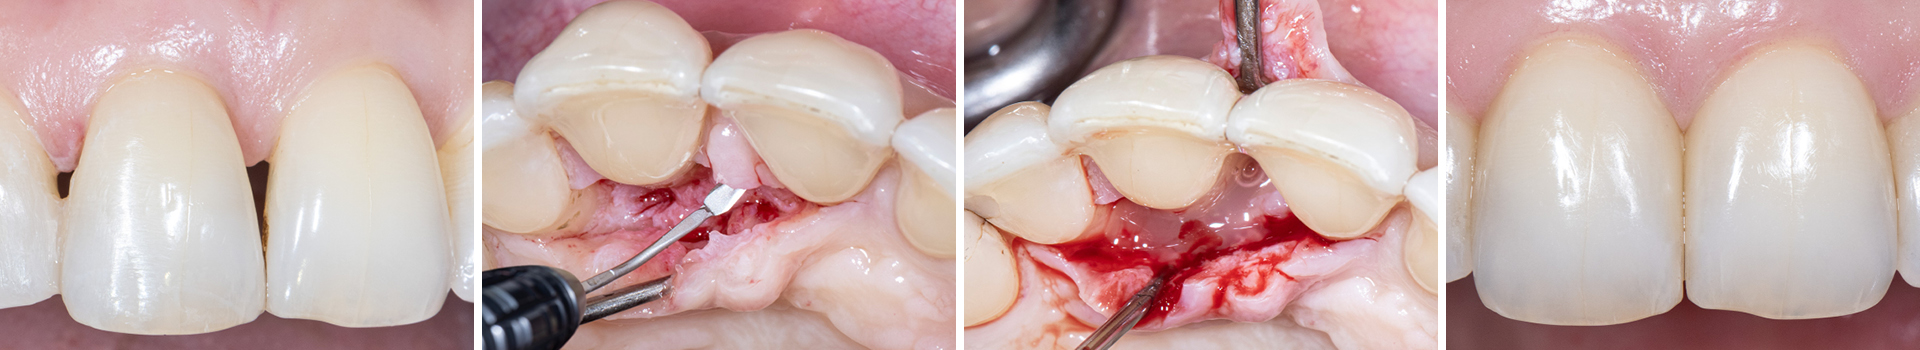

Regenerative Parodontalchirurgie mit anschließendem Kompositverschluss des Interdentalraumes

Nachfolgende Patientin ist 44 Jahre alt und wurde von ihrem Hauszahnarzt aufgrund ihrer Parodontitis an uns überwiesen. Sie ist allgemeinmedizinisch gesund und Nichtraucherin.

Während der intraoralen Untersuchung wurden eine erhöhte Beweglichkeit sowie erhöhte Taschensondierungstiefen und klinische Entzündungszeichen an Zahn 11 festgestellt. Ein intraorales Röntgenbild wurde angefertigt. Die intraossäre Defektkomponente gemeinsam mit dem hohen Niveau an Mundhygiene bieten eine gute Grundlage für einen regenerativ-parodontalchirurgischen Eingriff. Zehn Tage vor dem Eingriff wurde der Zahn mit dem Nachbarzahn verblockt und ein lokales Antibiotikum in die parodontale Tasche appliziert, um zum Zeitpunkt des Eingriffs möglichst entzündungsarme Verhältnisse vorzufinden. Unmittelbar vor Beginn des chirurgischen Eingriffs wurde der Defektboden mit einer Parodontalsonde ausgelotet, um Informationen über die dreidimensionale Defektmorphologie zu erhalten (Abb. 1-3).

Abbildung 1

Aufgrund der hohen Lachlinie haben wir uns für eine horizontale Inzision durch die Papillenbasis auf der palatinalen Seite sowie intrasulkuläre Inzisionen um die Nachbarzähne entschieden. Auf diese Weise können Oberflächeninzisionen auf der bukkalen Seite, die zu sichtbarem Narbengewebe führen können, vermieden werden.

Abbildung 2

Abbildung 3

Abbildung 4